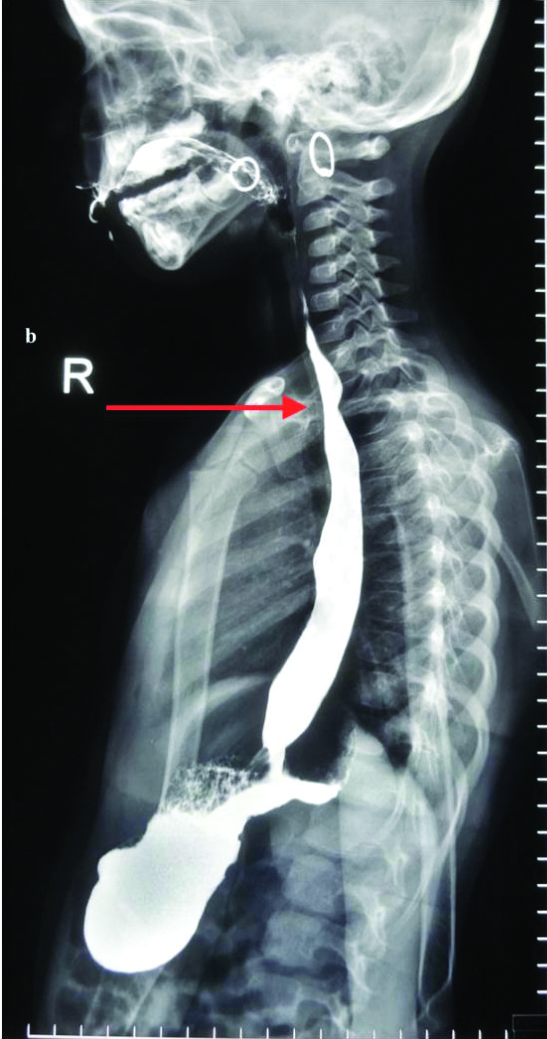

The twins were monozygotic and were weaned unsuccessfully at four months of age with semisolids. The first set of investigations included indirect and direct laryngoscopy, upper oesophago gastroduodenoscopy and oesophageal barometry but all test results were inconclusive. Computed Tomography (CT) and Magnetic Resonance Imaging (MRI) were also done and found to be inconclusive. Echocardiography was done to rule out any cardiac defects and was found to be normal. Finally, barium oesophagogram showed constant narrowing of the oesophagus at the level of the aortic arch without any evidence of mucosal irregularity. The narrowing had an oblique orientation from inferior left to superior right on the posterior aspect of the oesophagus. This was consistent with extrinsic compression by a retro-oesophageal aberrant right subclavian artery in both the patients [Table/Fig-1a,b]. Based on the above findings, operative repair was advised.

Spot film from barium oesophagogram in other twin showing similar finding consistent with aberrant right subclavian artery.